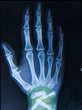

骨髓炎诊断不难,患者出现骨痛、发冷、发热、行走困难的症状即可初步诊断为骨髓炎,如果患者ESR和C-反应蛋白增高,X线发生变化,3-4周后,可见损伤部位肿胀、骨破坏、骨变短、软骨下骨板侵蚀即可最终确诊为骨髓炎。如果患者X线没有发生变化,要再做CT检查,检查结果为病变骨及椎旁脓肿即可最终确诊为骨髓炎。为了区别骨折和肿瘤,患者还可以做穿刺活检、手术活检、药敏试验。

髓炎X线显示骨膜反应,骨破坏这种类型最多,一般变化为弥漫性,急性进程的病例诊断不会困难,而亚急性或慢性发病,疼痛轻,全身及局部炎症症状轻的病例,与骨肿瘤性疾病的鉴别非常困难,一般而言,这种骨髓炎的X线片,骨髓腔内的变化比较轻微,骨膜反应为全周性且范围广泛,有时骨皮质的一部分发白,硬化,成死骨像,这是一特点,肿瘤性疾病不能见到。